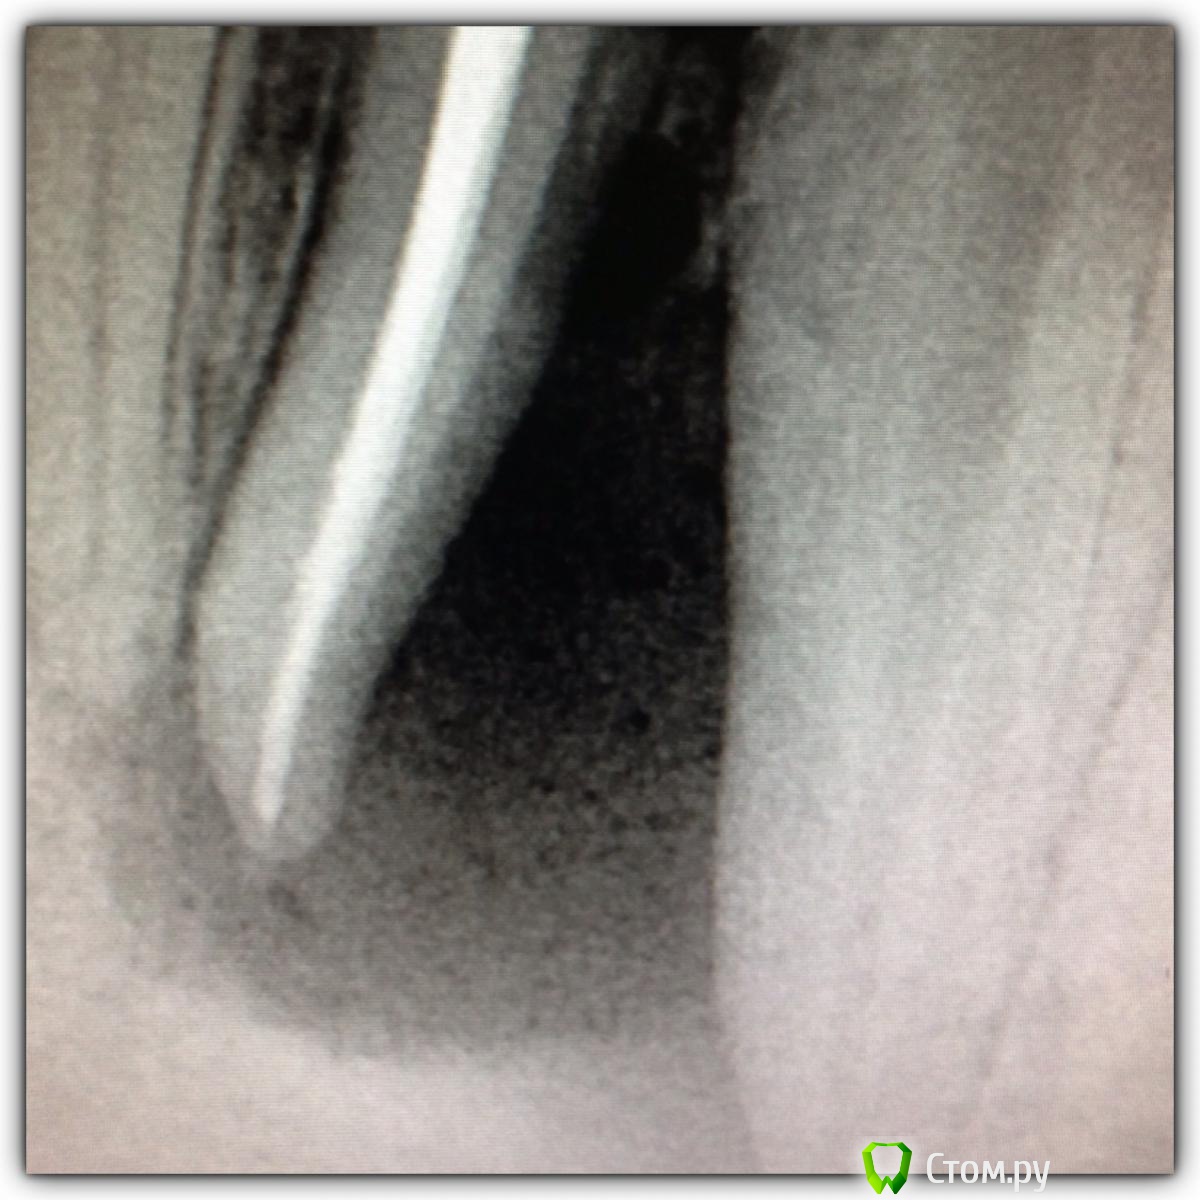

SSTi Опубликовано 16 октября, 2014 Автор Поделиться Опубликовано 16 октября, 2014 46. Пульпит. По приказу свыше. Убрал бломбу, каривус. Коффер. Открываемся. Полость склерозирована. В ней- дентикль. Уз убрал. В каналы только десятка заходит. Долго долго расширял. Очень долго. Дистальные 25.06, 30.04 профайл. Медиальные 20.06, 25.04. Ирригация стандартная. И очень обильная. Дистальные сходится. П.с. Про кость знаю. 5 Ссылка на комментарий

Гарриевич Опубликовано 16 октября, 2014 Поделиться Опубликовано 16 октября, 2014 хорошо, но бессмысленно)и еще, когда такая ситуация с костью, лучше проводить через кальций Ссылка на комментарий

M@estro Опубликовано 16 октября, 2014 Поделиться Опубликовано 16 октября, 2014 хорошо, но бессмысленно)и еще, когда такая ситуация с костью, лучше проводить через кальций И коронку на золоте, один фиг - без гарантии Ссылка на комментарий